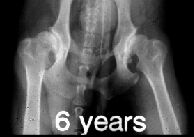

Zdravé kloubyTěžká DKK

Na levém snímku můžeme vidět kyčelní klouby zdravého zvířete, ale na druhém snímku je zrentgenované zvíře postižené těžkou dysplazií.